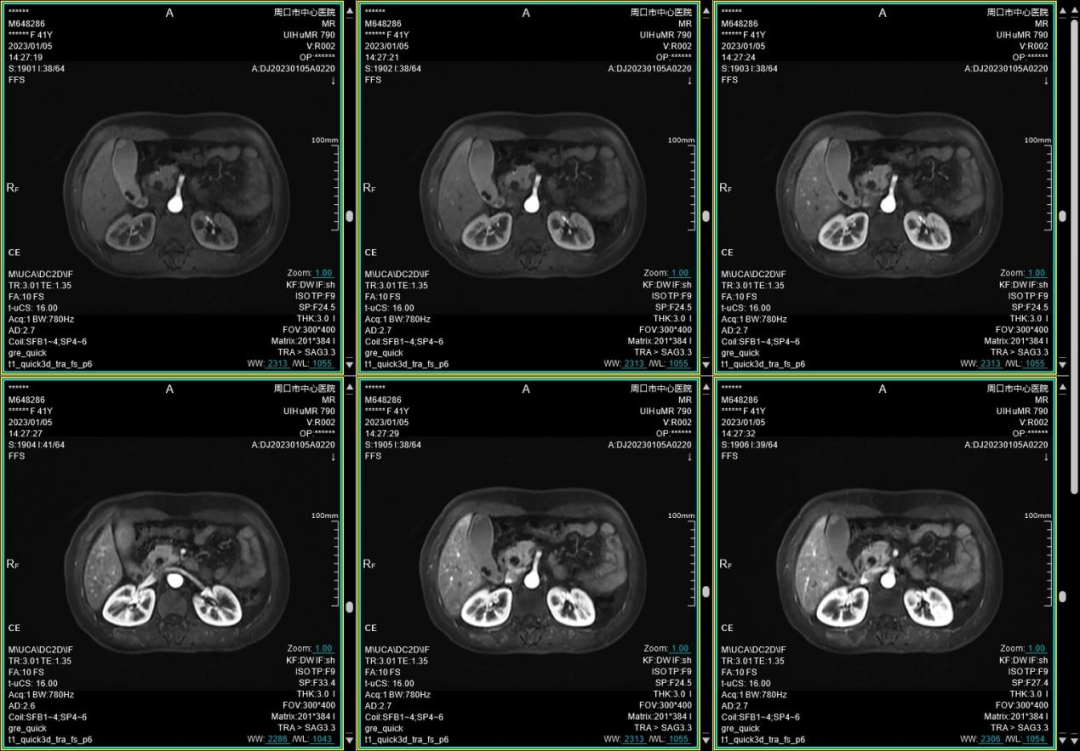

(腹部超高时间分辨率动脉期多时相扫描)

此外,联影智能光梭uMR790 3.0T 磁共振具有丰富的扫描检查模式,能够完成包括神经系统、胸部、腹部、盆腔、心血管、骨骼关节、软组织、乳腺等全身各部位磁共振检查,并且能够完成以前不能进行的胸部等部位磁共振检查。不同序列能够对组织结构和病灶进行多角度、多方位观察,利于病灶定性分析,同时,能够大大提高较多、较小病灶的检出率,做到早发现、早治疗、提升患者后续生活质量。并且可以大量应用于全身各部位的功能成像,能够详细地观察人体各器官结构和病变的形态学变化,有利于疾病的诊断和鉴别诊断。

周口市中心医院磁共振室现已全面开展各项磁共振高级功能成像(包括SWI、PWI、BOLD、MRS、DTI等)、胎儿、乳腺、心脏、颞颌关节、动脉高分辨血管壁分析以及周围神经等检查,陆续开展磁共振介入和磁共振高级科研临床应用。磁共振功能成像广泛应用于临床各科,如神经内外科、肝胆内外科、心内科、小儿科、妇产科、泌尿科、肿瘤内外科等临床各个学科,这些极其优秀的特色MR成像技术,大大提高临床疑难疾病的诊断符合率,更有助于临床医生更准确有效及时的治疗,让患者得到更优质的康复。比如,DTI用于脑肿瘤对正常白质纤维束的侵占,术前和术后对于治疗效果的评估,可以更准确地反映白质纤维束的空间走向。在心血管领域突破了心脏禁区,可全面评估,心脏大血管解剖结构成像、心肌功能分析等全方位的检查研究,大大方便了中老年心脏病患者。在体部领域实现了肝脏三维容积超快速多期动态增强检查,可以敏感发现早期微小肝癌,不会遗漏边缘部位和微小病变。充分利用GE 3TMR“乳腺微观成像”高分辨展示乳腺结节、导管及淋巴结转移;“磁共振灌注成像”界定急性脑梗塞的缺血半暗带;“波谱成像”能真正在活体(病人)上分析化学成分。因此,努力提升MRS、SWI、DTI、PWI、CEMRA、腹部MR平扫及增强等MR功能成像业务,极大程度地避免了病人要到外地就医问题,也进一步提升了科室技术水平,并能获得良好的社会效益和经济效益。MR引导下穿刺活检及介入治疗。